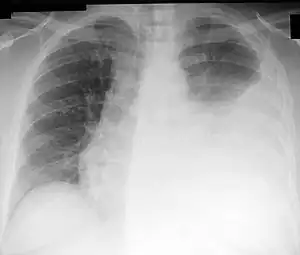

Chest X-ray showing a left-sided pleural effusion (right side of image) that was than treated with thoracentesis.